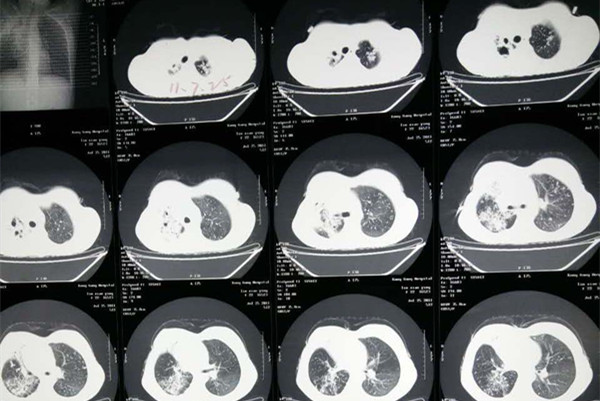

该病发病时典型症状主要是出现不同程度的发热、盗汗、乏力等,其中也有表现胸痛,如果胸腔存在大量积液时可能会出现呼吸困难。所以察觉自己有这些症状一定要及时去相关医疗机构检查确诊是否是结核病。